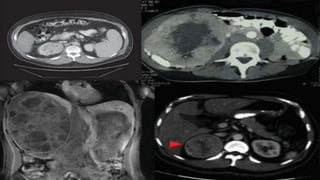

• 64-yr-old man presents with right flank pain, no hematuria

• Past medical history includes:

• Mild hypertension (140/85 mmHg, not on medication),

hypercholesterolemia, no other cardiac history

• 20 pack-yr smoker

• Family history: negative for cancer

• Physical exam: right flank fullness, otherwise normal

• ECOG PS 0

• Labs: hemoglobin: 11.0 g/dL, ANC and platelets normal,

creatinine: 1.2 mg/dL, LDH: 287 U/L, calcium normal